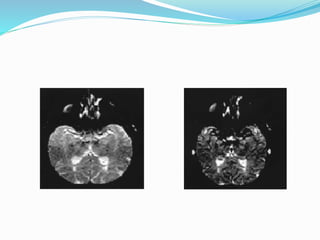

Endogenous Tracer Methods Arterial Spin Labeling MR

Imaging

 Arterial blood flowing towards the region of interest is

tagged by magnetic inversion pulses (proton phase is

changed).

↓

 After a delay to allow for inflow of tagged blood,

image is acquired in slice of interest. This image is

called ‘tag image’.

 Second image without in-flowing tagged blood. This

image is called ‘control image’.

 Tag image is subtracted from control image

 This results into perfusion image representing ‘tagged

blood’ that flowed into the image slice.

 It has poor SNR, however, ASL has better spatial and

temporal resolution than PET. Poor SNR and

sensitivity to abnormally long transit delays of tagged

protons prevents its general application.